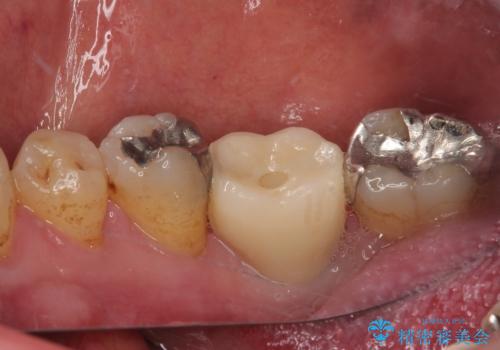

- 奥歯を抜歯してから放置しているとのことで来院された患者様です。

歯が割れて抜歯になってしまったとのことで、咬合力に抵抗できるよう、インプラントによる補綴治療を行うこととしました。

むし歯の放置期間と抜歯してからの放置期間が長く、咬み合わせる上顎の歯がやや伸び出している状態でした。

上顎の部分矯正や対合歯の補綴治療も提案しましたが、今回は欠損部のみの治療を行いました。